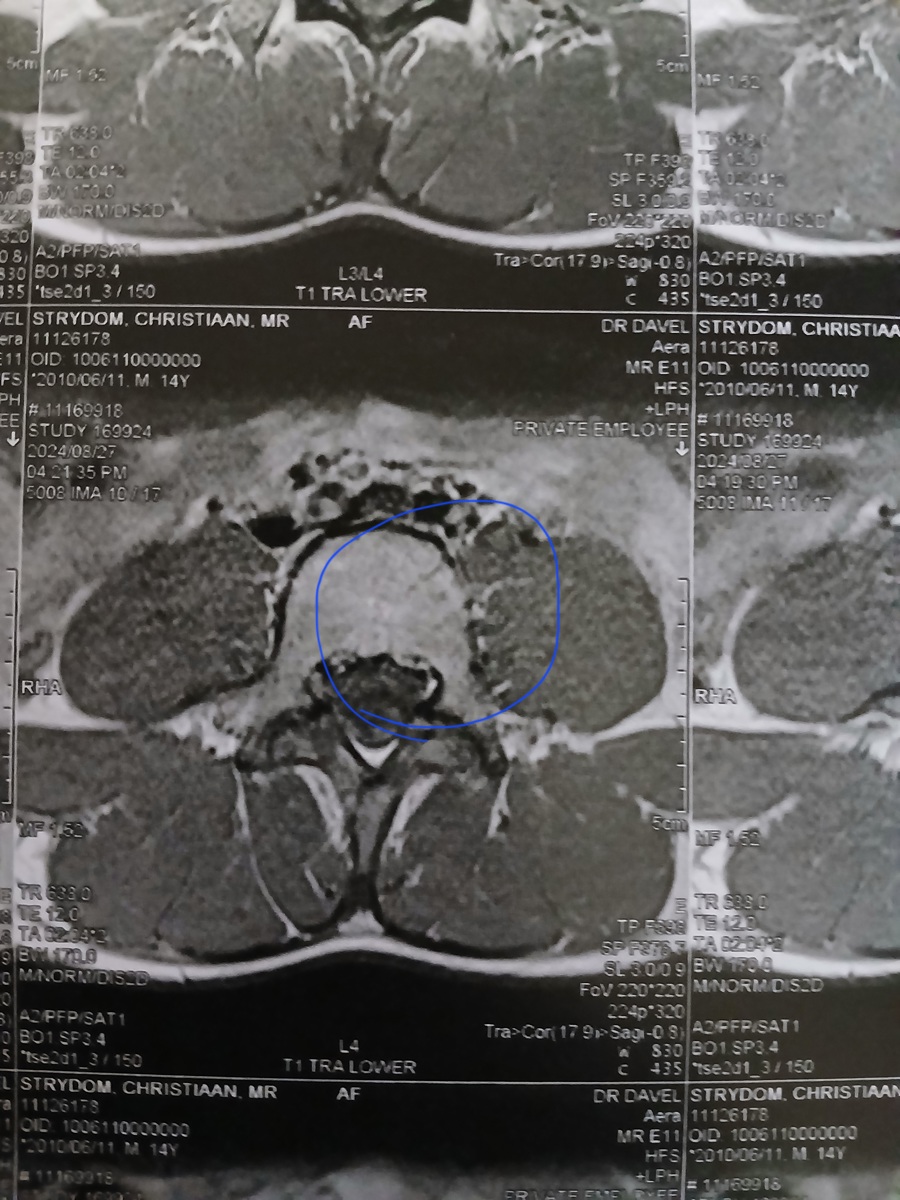

My seun Christiaan Strydom is 14 jaar oud en het die 20ste Julie 2024 ‘n beseering in ’n rugby wedstryd op gedoen. Hy het 3 van sy werwels gebreek en gekraak. Dit is sy T12, L4 en L1. Sy T12 is die ernstig gebreek maar alles is darem nog in plek wat baie goed is. Hy kry van die voorval sukkel oomblike as hy lank reg op sit of vêr of baie loop dan begin sy liggaam onbeheerlik te ruk. En dan is hy in vreeslik baie pyn en hy kan deesdae nie sy hande gebruik of loop dan nie. Hy het nog die krag in sy bene maar hy kan dit nie optel om te loop nie. Dit het in die begin so een keer ‘n week gebeur, maar die laaste twee weke gebeur dit een keer ’n dag. En dit is as of die gevoel in sy bene al hoe langer vat om reg te kom. Hy was tot vandag (12/09/2024) deur die Neurochirug dokters gesien en behandel by die Polokwane Provinsiale Hospitaal. Hulle het ons vandag verwys na die Spinale Ortopediese dokters toe wat ons eers die 1st Oktober ‘n afspraak by gekry het. Omdat ek nie ’n SASSA kaart het nie moet ons elke keer as hy hospitaal toe gaan om dokters te sien R350 betaal. Ons kon tans nie daar...